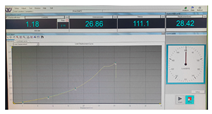

| Fracture force graphic |  |  |  |

| Fracture force graphic |  |  |  |

| Fracture force graphic |  |  |  |

| Fracture force graphic |  |  |  |

| Fracture force graphic |  |  |  |

| Fracture force graphic | N.A. | N.A. | N.A. |